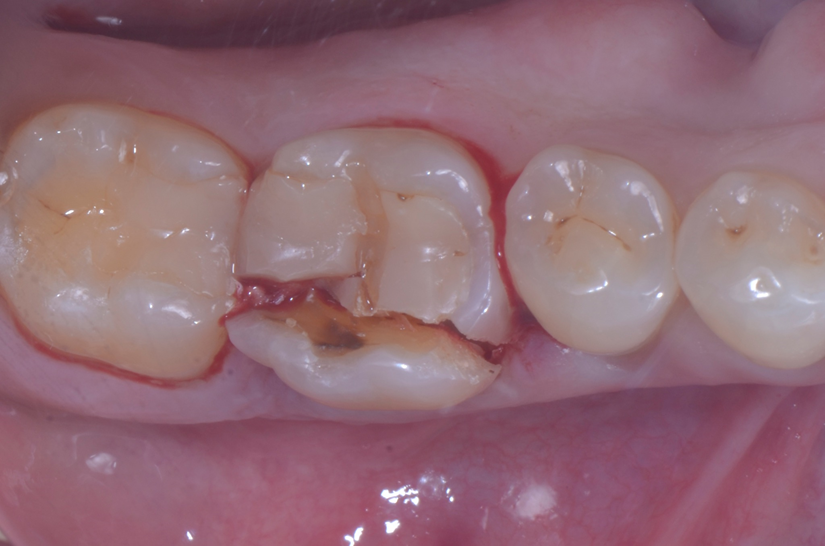

O paciente apresentou fratura vertical mésio-distal no elemento 46. Foi planejada a exodontia minimamente traumática e instalação imediata do implante Maestro Superiore (Implacil Osstem) utilizando uma guia prototipada. Após a exodontia, o implante foi instalado seguindo o protocolo de cirurgia guiada. O GAP vestibular foi preenchido com o Extra Graft. Um cicatrizador personalizado impresso com haletas facilitadoras foi capturado com resina flow e instalado. Após 30 dias, foi realizado escaneamento indireto para obtenção do perfil de emergência, utilizando protocolo digital com sobreposição do cicatrizador escaneado para confecção da coroa definitiva em zircônia policristalina estabilizada por ítria.

A aplicação de biomateriais como o Extra Graft no preenchimento do GAP tem por objetivo preservar o volume alveolar e otimizar a cicatrização3,4. Estudos apontam que o uso de biomateriais associados ao implante imediato resultam em menor reabsorção óssea horizontal e vertical5.